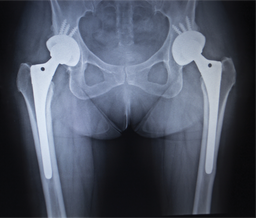

Traditional encapsulants, mostly used for macroscopic objects such as pacemakers or Cochlear devices, include metals, ceramics, and polymers. Their downside is their thickness and robustness which increases the mass and dimensions of the implant, and decreases its comfort of use. Also, when the implant size diminishes, and the requirements for the implant lifetime increase, novel encapsulation methods are called for. |

ALD offers a truly sophisticated, proven method for reliable, hermetic, protective encapsulation of various implantable devices, from microelectronic sensors to macroscopic items such as orthopaedic and dental implants.